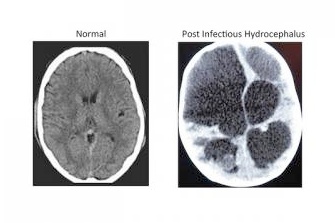

Hydrocefalus neboli vodnatelnost mozku je abnormální stav, při kterém se v mozku hromadí mozkomíšní mok. Následkem je nitrolební hypertenze, rozšiřování hlavy a mentální postižení, v těžkých případech i smrt. Hydrocefalus je nejčastějším důvodem neurochirurgických zákroků u dětí. V subsaharské Africe se ročně vyskytne asi 100 000 případů, které se rozvinou jako následek infekčních onemocnění, nejčastěji neonatální sepse. Ta se objevuje během prvních čtyř týdnů života a ve věku tří až čtyř měsíců se mnoho dětí objeví u lékaře znovu – tentokrát s rostoucí hlavou.